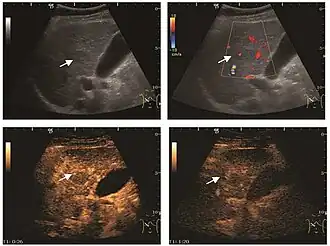

These lesions have various patterns (hypo or hyperechoic) with at least 1 cm diameter. They are hepatocytes with dysplastic changes, but without clear histological criteria for malignancy. They are divided into low-grade dysplastic nodules, where cellular atypia are mild and high-grade dysplastic nodules with moderate or severe cellular atypia, but without any established signs of malignancy. Occasionally, well-differentiated HCC foci can be identified in high-grade dysplastic nodules (appearance called "nodule in nodule") . Most authors accept the carcinogenesis process as a progressive transformation of DN from low-grade to high-grade and into HCC. The nodule's vasculature changes progressively, correlated with the degree of malignancy, and it is characterized by decrease until absence of portal venous input and by increase of arterial intratumoral input. Neoformation vessels occur with increasing degree of dysplasia. Arterial neovascularization is enhanced in a chaotic and explosive way, while normal, arterial and portal vasculature continues to decline. High-grade dysplastic nodules are hypovascularized both arterial and portal phases, while early HCC nodules may have similar arterial pattern with the surrounding parenchyma or exacerbated, and portal hypovascularization. In moderate or poorly differentiated HCC (classic HCC) tumor nutrition is performed only by neoformation vessels (abundant), the normal arterial and portal vasculature completely disappearing. This behavior of intratumoral vascularization is typical for HCC and is the key to imaging diagnosis.

B-mode ultrasonography is unable to distinguish between regenerative nodules and borderline lesions such as dysplastic nodules and even early HCC. Doppler examination also has a low sensitivity in differentiating dysplastic nodules from early HCC. Doppler signal may be absent in both regenerative and dysplastic nodules. Some authors indicate the presence of venous type Doppler flow which reflects the portal venous nutrition of the nodule as a characteristic feature of dysplastic nodules and early HCC (Minami & Kudo, 2010). Other authors noticed the presence of an arterial flow with small frequency variations and a normal resistivity index. On CEUS examination both RN and DN may have quite a variable enhancement pattern. Generally, both nodules enhances identically with the surrounding liver parenchyma after UCAs injection. Dysplastic nodules are hypovascular in the arterial phase. In case of highgrade dysplastic nodule sometimes a hypervascularization can be detected, but without associating "wash out" during portal and late CEUS phases. In these cases, biopsy may clarify the diagnosis.

On CEUS examination, early HCC has an iso- or hypervascular appearance during the arterial phase followed by wash out during portal venous and late phase. There are studies showing that the wash out process is directly correlated with the size and features of neoplastic circulatory bed. Thus, highly differentiated HCC illustrates the phenomenon of late or even very late "wash out" while poorly differentiated HCC has an accelerated wash out at the end of arterial phase. It is therefore mandatory to analyze all these three phases of CEUS examination for a proper characterization of liver nodules. Tumor wash out at the end of the arterial phase allows the HCC diagnosis with a predictability of 89.5%. Some authors consider that early pronounced contrast enhancement of a nodule within 1–2 cm developed on a cirrhotic liver is sufficient for HCC diagnosis. These results prove that for a correct characterization of the lesions it is necessary to extend the examination time to 5 minutes or even longer.